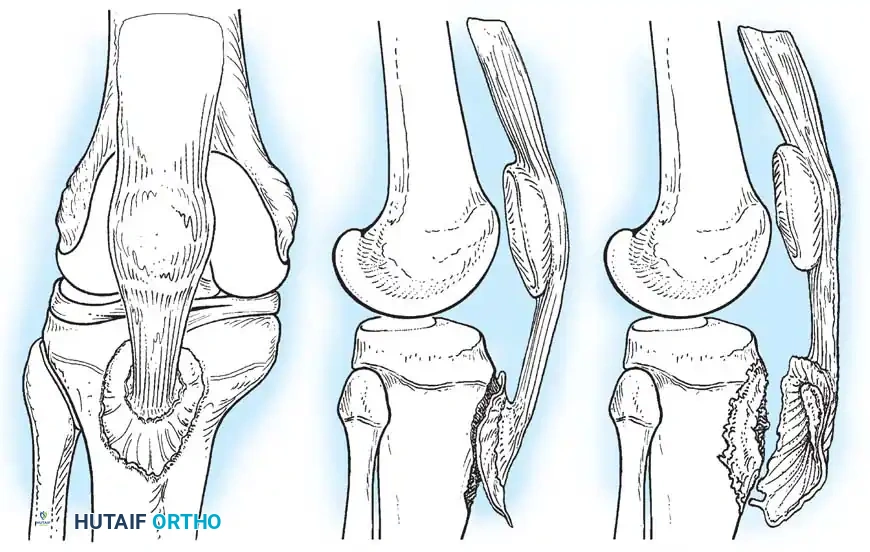

Classification (Meyers and McKeever)

The management of tibial eminence fractures is dictated by the Meyers and McKeever classification system, which assesses the degree of displacement and the presence of a cartilaginous hinge.

- Type I: Non-displaced or minimally displaced fracture. The bony fragment rests in its anatomical bed.

- Type II: The anterior portion of the eminence is elevated and displaced proximally, but an intact cartilaginous hinge remains posteriorly. The fragment resembles a bird's beak.

- Type III: Complete displacement of the fragment with no cortical or cartilaginous continuity. The fragment may be rotated.

- Type IV (Zaricznyj modification): Comminuted fracture of the eminence.

Clinical Pearl: The most significant complication of a displaced tibial eminence fracture is not anterior instability, but rather a mechanical block to terminal extension. The displaced fragment impinges against the intercondylar notch of the femur.

A critical factor in the failure of closed reduction is the interposition of soft tissue beneath the avulsed fragment. Kocher et al., in a review of 80 skeletally immature patients, identified entrapment of the anterior horn of the medial meniscus, the intermeniscal ligament, or the anterior horn of the lateral meniscus in:

* 26% of Type II fractures.

* 35% of Type III fractures.

Because of this high rate of soft-tissue interposition, forceful attempts to reduce Type III fractures by simply extending the knee are contraindicated, as this can further crush the entrapped meniscus.